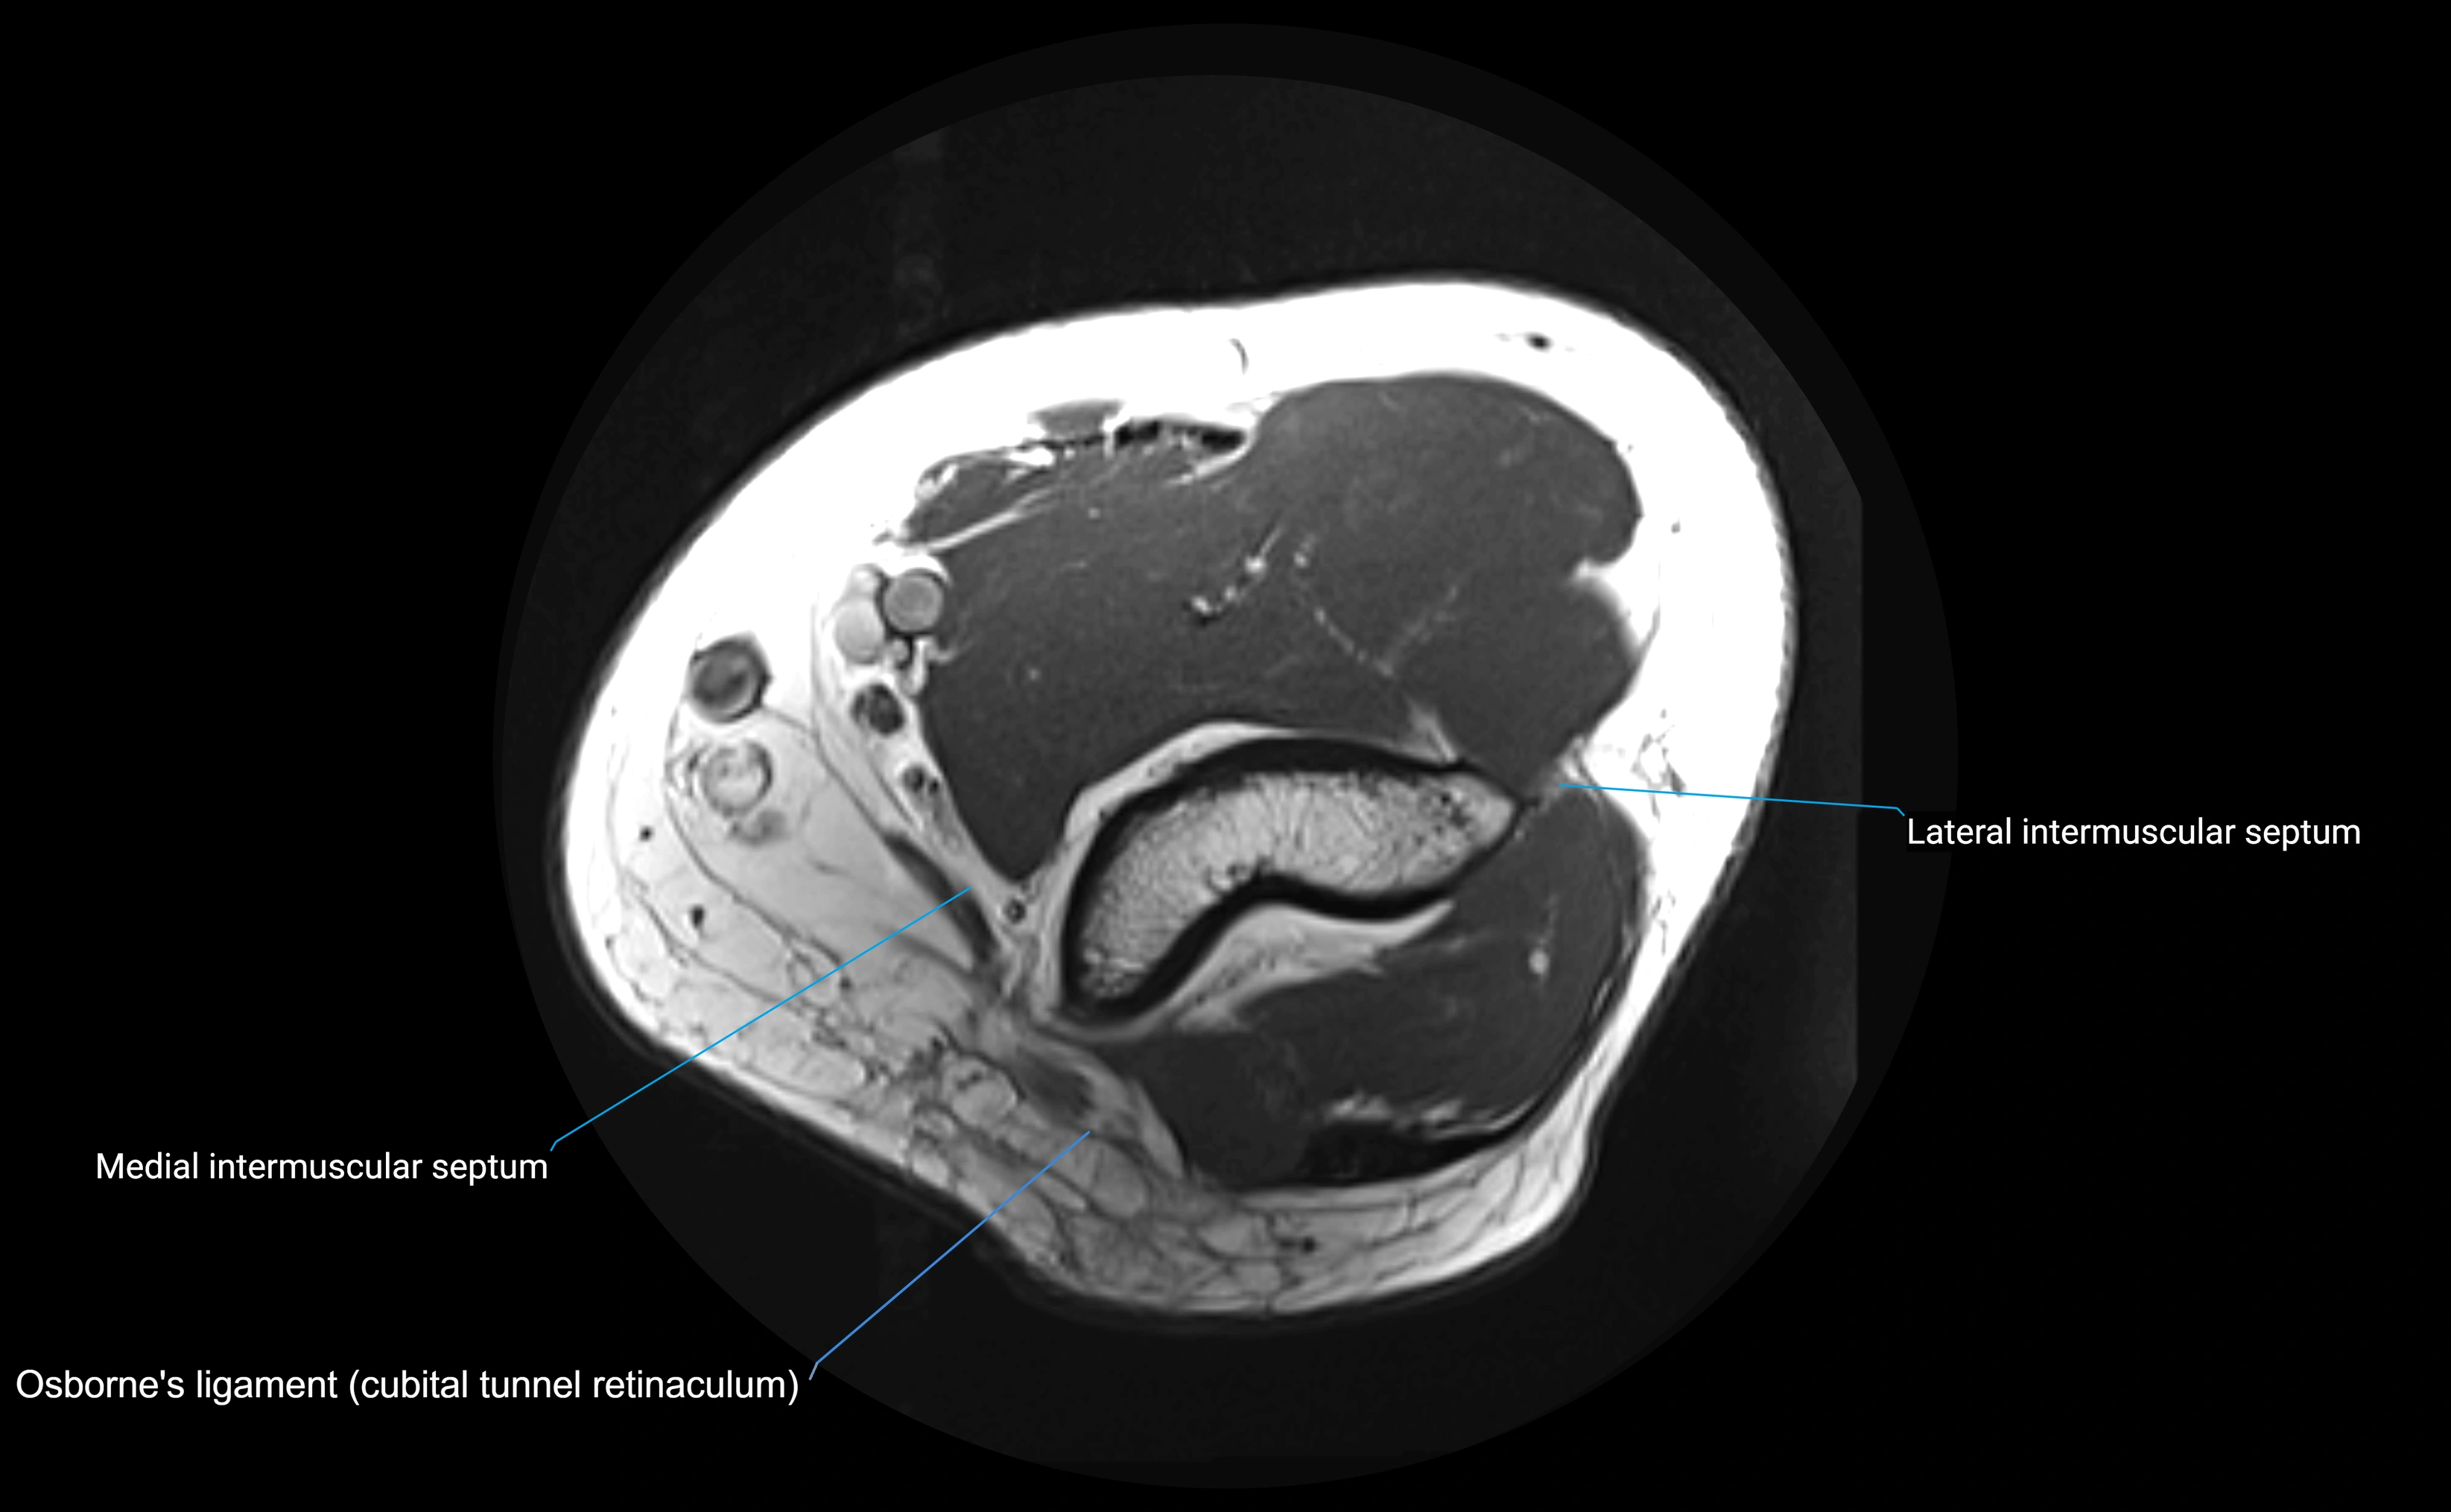

MRI Appearance

T1-weighted images:

• Ligament: low signal intensity (dark), appearing as a continuous band around the radial head.

• Adjacent fat and marrow: bright, creating contrast with the ligament.

• Thickening or disruption indicates injury or fibrosis.

• Joint capsule and synovium seen as thin low-signal lines contiguous with ligament margins.

T2-weighted images:

• Ligament: low signal (dark) with clear delineation from joint fluid.

• Fluid or edema: bright hyperintense, separating or surrounding the ligament in partial tears.

• Complete tear: discontinuity or non-visualization of ligament fibers, often with joint effusion.

MRI images

image